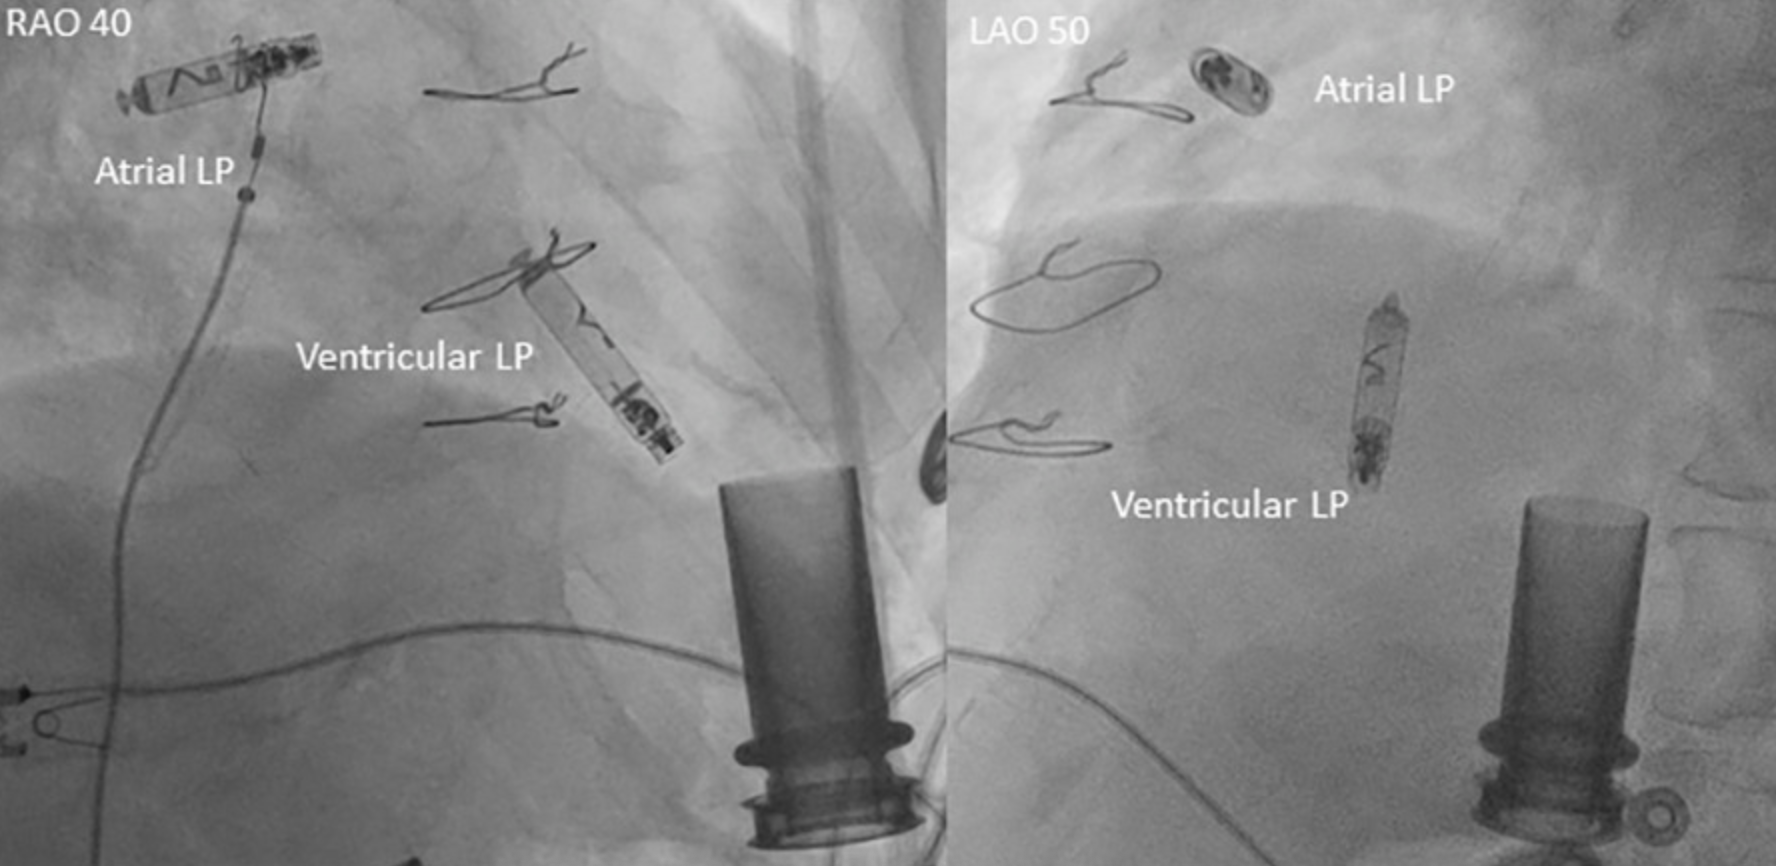

图3 心室和心房无导线起搏器释放后最终影像

• 在术后第二天以及术后两周的随访中,心房LP与心室LP均未受到电磁干扰,同时,两者之间的i2i通信以及与程控仪之间的通信均无异常(图4)。

• 本文报道了首例在装有Heartmate II左心室辅助装置的患者体内植入AVEIR DR双腔无导线起搏系统的病例,术中植入过程安全,术后器械通信正常,结果满意;